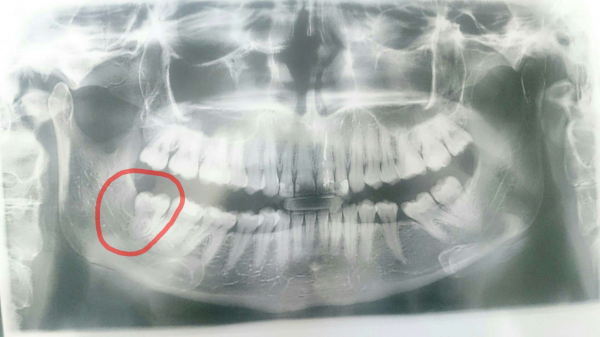

Полгода назад у меня начал расти зуб мудрости, но он полностью не может вылезти. Хирург сказал, что зуб нужно будет удалять со временем. Три дня назад зуб снова начал расти, стало больно глотать, рот полностью больно открыть. На ощупь на шее внизу челюсти под зубами увеличился, лимфоузел. Температуры нет.

Да, скорее всего, нужно будет удалять зуб в ближайшее время. Лимфоузлы воспалились по этой же причине от зуба. Температура не всегда бывает. Запишитесь на консультацию к специалисту.